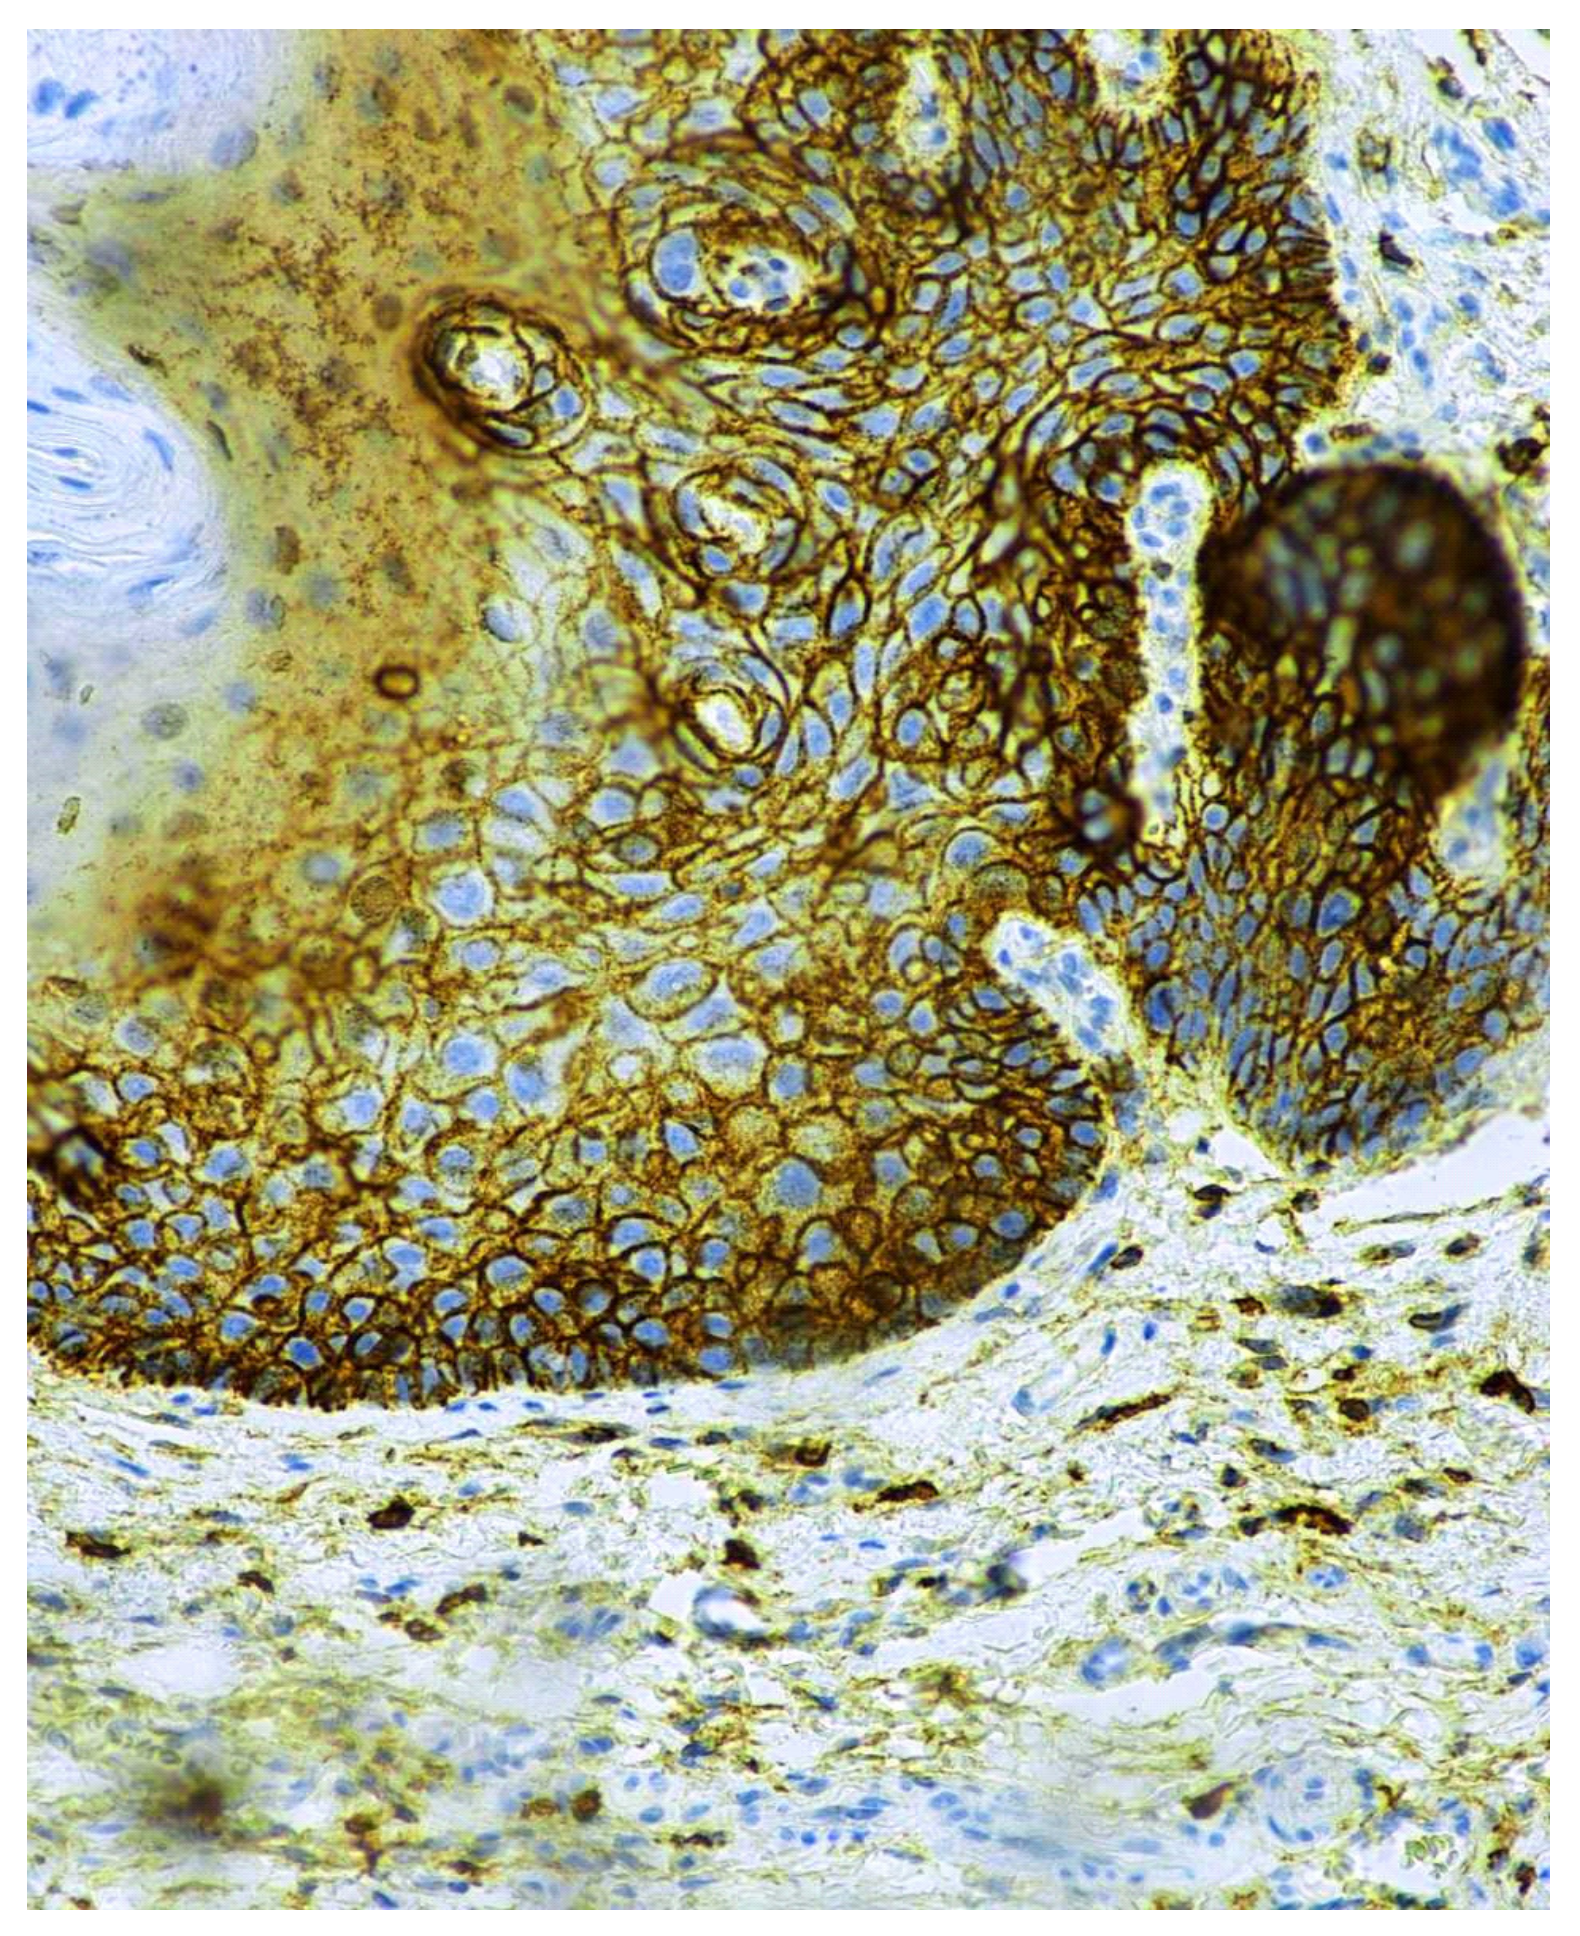

3.2. Immunohistochemical CD44 Antigen Characteristics

- Dzudzilo, M.; Kleina, R.; Čēma, I.; Dabuzinskiene, A.; Svirskis, Š. Expression and Localisation of CD44 Antigen as a Prognostic Factor of Oral Leukoplakia. Proc. Latv. Acad. Sci. Sect. B Nat. Exact Appl. Sci. 2021, 75, 68–74. [Google Scholar] [CrossRef]